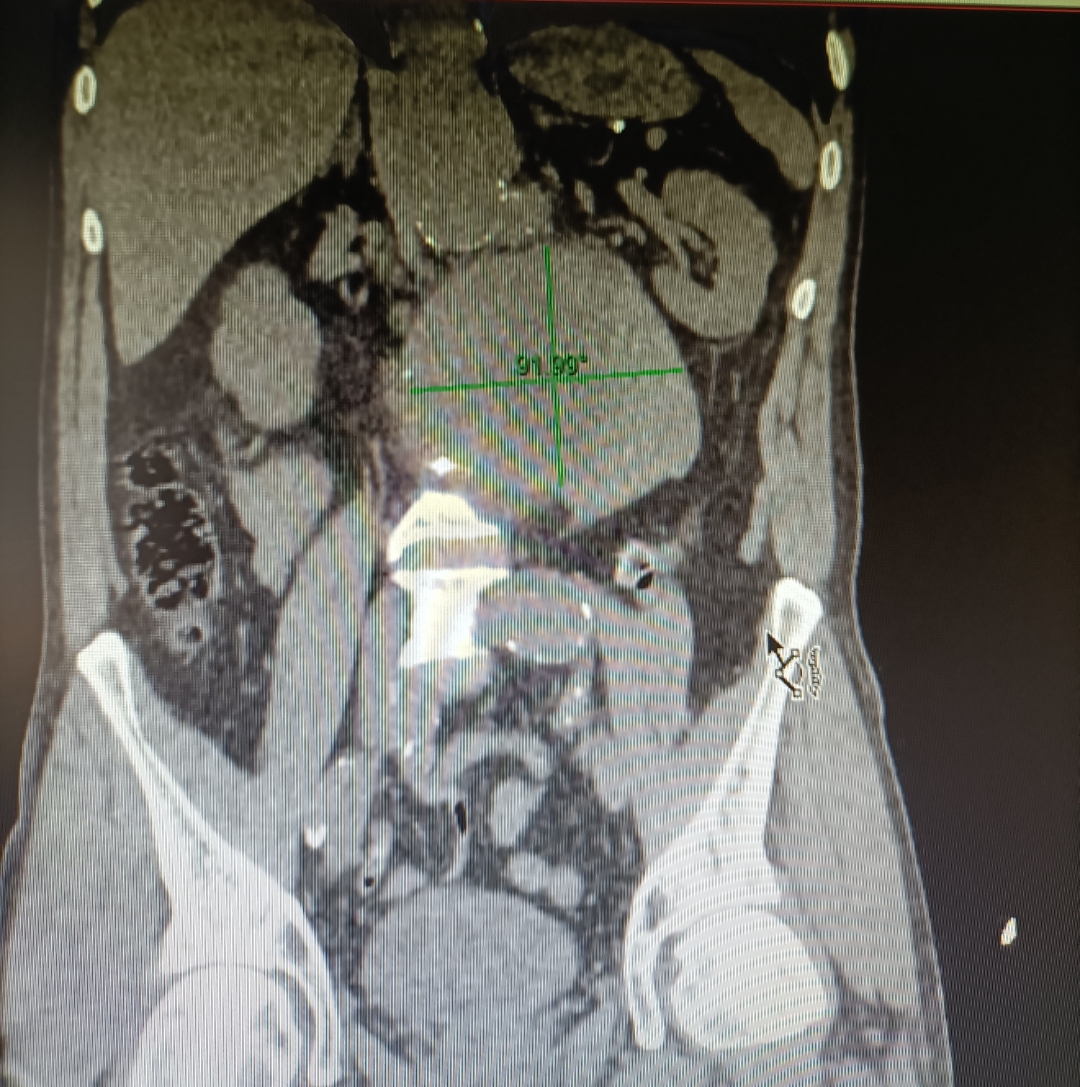

Se medica para control del dolor y se realiza Angio-TC de abdomen, donde se observan hallazgos compatibles con aneurisma de aorta abdominal infrarrenal de unos 14 x 13 cm que se extiende hasta bifurcación ilíacas, con calcificación intimal y trombo semilunar, con signos de rotura inminente.